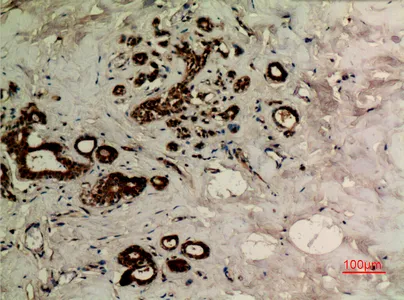

KiSS-1R Rabbit Polyclonal Antibody

Cat: APRab13039